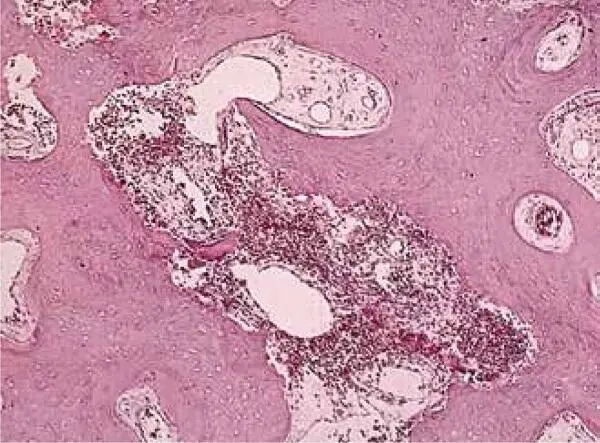

FIG 1-18Histomorphometry of an autogenous bone graft without PRP at 4 months shows that the graft has a 60% trabecular bone density, consists mostly of immature bone, and is undergoing active resorption-remodeling. (Reprinted with permission from Marx and Garg. 1)